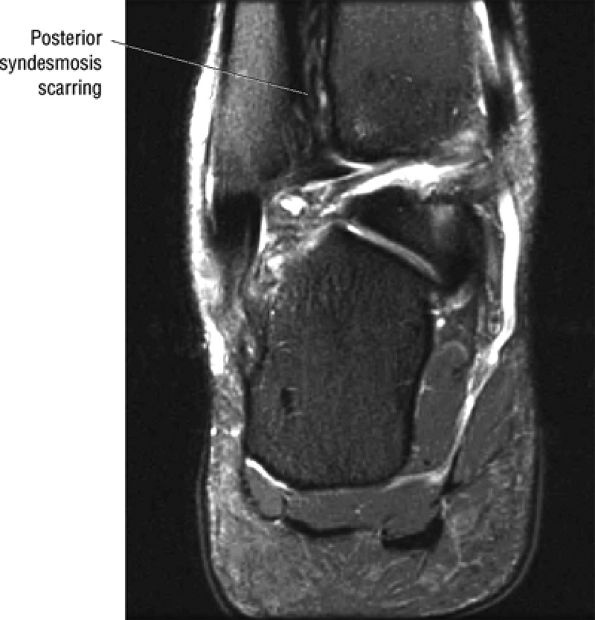

FIGURE 5.67 ● Posterior coronal FS PD FSE image at the level of the posterior talofibular ligament (PTF) and posterior tibiotalar ligament (PTT). TP, tibialis posterior; FDL, flexor digitorum longus; PB, peroneus brevis tendon; PL, peroneus longus tendon.